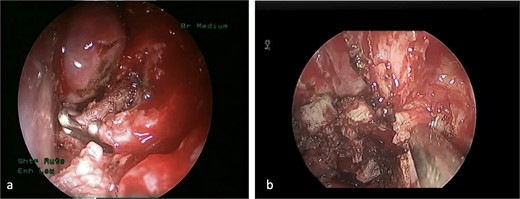

This is a case of a 12-year-old male complaining of nasal obstruction and denying epistaxis, headache, and nasal discharge symptoms. He was found to have bilateral JNA and was successfully treated with embolization of the bilateral distal IMA using polyvinyl alcohol (PVA) particles, followed by surgery. A subtotal resection of the nose, involved sinuses, pterygopalatine fossa, and infratemporal fossa was performed with no postoperative complications (Fig. 8). Six months later, the patient had a recurrence. An in-office endoscopic examination revealed a right-sided mass on the posterolateral wall, necessitating resection. One month prior to surgery, the patient was managed in the emergency department for persistent right-sided epistaxis. It lasted for eight hours and was successfully managed with tranexamic acid. CT imaging showed the recurrent right nasopharyngeal mass with skull extension into the sphenoid sinuses and the right pterygoid plate (Fig. 7a and b). Hence, he underwent embolization of the ECA (Fig. 7c–e). The patient subsequently experienced a decreased level of consciousness, aphasia, and right-sided weakness, with a power of 2/5 in both the lower and upper limbs. MRI showed multiple, extensive punctate foci of cortical and basal ganglia acute infarction complicated by edema, predominantly affecting the left side without a hemorrhagic component. Findings are consistent with showering from the PVA particles (Fig. 7f). A total of 12 months later, the patient was recovered and cleared neurologically to undergo endonasal endoscopic removal for the tumor. The patient was treated surgically at another institution, followed by a course of radiotherapy. Thereafter, he resumed his follow-up in our center, showing no evidence of recurrence after 1 year of follow-up.

(a) The sphenopalatine artery is clipped before tumor removal. (b) The vascular tumor is dissected from sphenoplataine and pterygopalatine fossa.